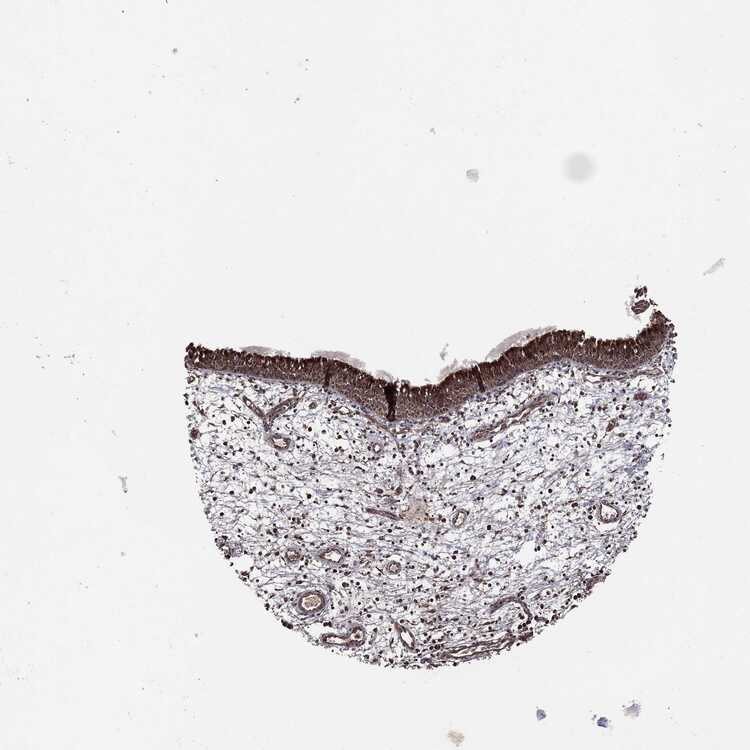

TISSUE PRIMARY DATA NASOPHARYNX Show tissue menu

Nasopharynx

NASOPHARYNX - Antibody stainingi

Antibody staining in the annotated cell types in the current human tissue is reported as not detected, low, medium, or high, based on conventional immunohistochemistry profiling in selected tissues. This score is based on the combination of the staining intensity and fraction of stained cells.

Each image is clickable and will lead to virtual microscopy that enables deeper exploration of all samples and also displays staining intensity scores, fraction scores and subcellular localization as well as patient and tissue information for each sample.

Ciliated cells (cell body) Medium------

Respiratory epithelial cells -HighMediumLowMediumHighHigh